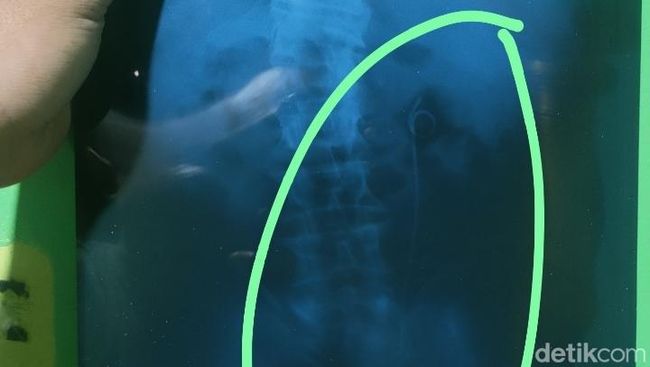

Penampakan selang yang disebut tertinggal di tubuh pria Batang, Jumat (26/9/2025).(Foto: Robby Bernardi/detikJateng)

Heboh ada selang tertinggal di saluran kencing pasien usai operasi. Direktur RSUD Kalisari Batang, Any Rusydiani memberi penjelasan.

Any menjelaskan selang yang masih berada di tubuh pasien itu bukan tertinggal. Selang itu dipasang sementara dan akan dilepas saat kondisi pasien sudah membaik.

"Kalau terkait dengan selang yang tertinggal dalam bahasanya, itu adalah satu rangkaian prosedur dari operasi pengambilan batu saluran kencing. Jadi selang itu dipakai untuk mempertahankan saluran antara ginjal sama kandung kemih," kata Any, saat ditemui awak media di RSUD Kalisari Batang, dilansir detikJateng, Selasa (30/09).

"Itu kan salurannya kecil, kalau habis operasi itu kan mesti ada sisa-sisa darah, sisa-sisa butiran-butiran pasir mungkin yang dari batunya. Nah itu dimaksudkan untuk memperlancar aliran sisa-sisa itu dari ginjal ke kandung kemih. Karena kalau tidak ada selang itu tambah justru sakit," imbuhnya.

Dengan selang tersebut, menurut Any, saluran itu tetap terbuka dan melancarkan sisa operasi atau sisa kristal dari baru di saluran ginjal.

"Untuk melancarkan sisa-sisa operasi atau sisa-sisa kristal-kristal yang ada dari batu di saluran ginjal sampai ke kandung kemih, itu (selang) dipasang," tambahnya.